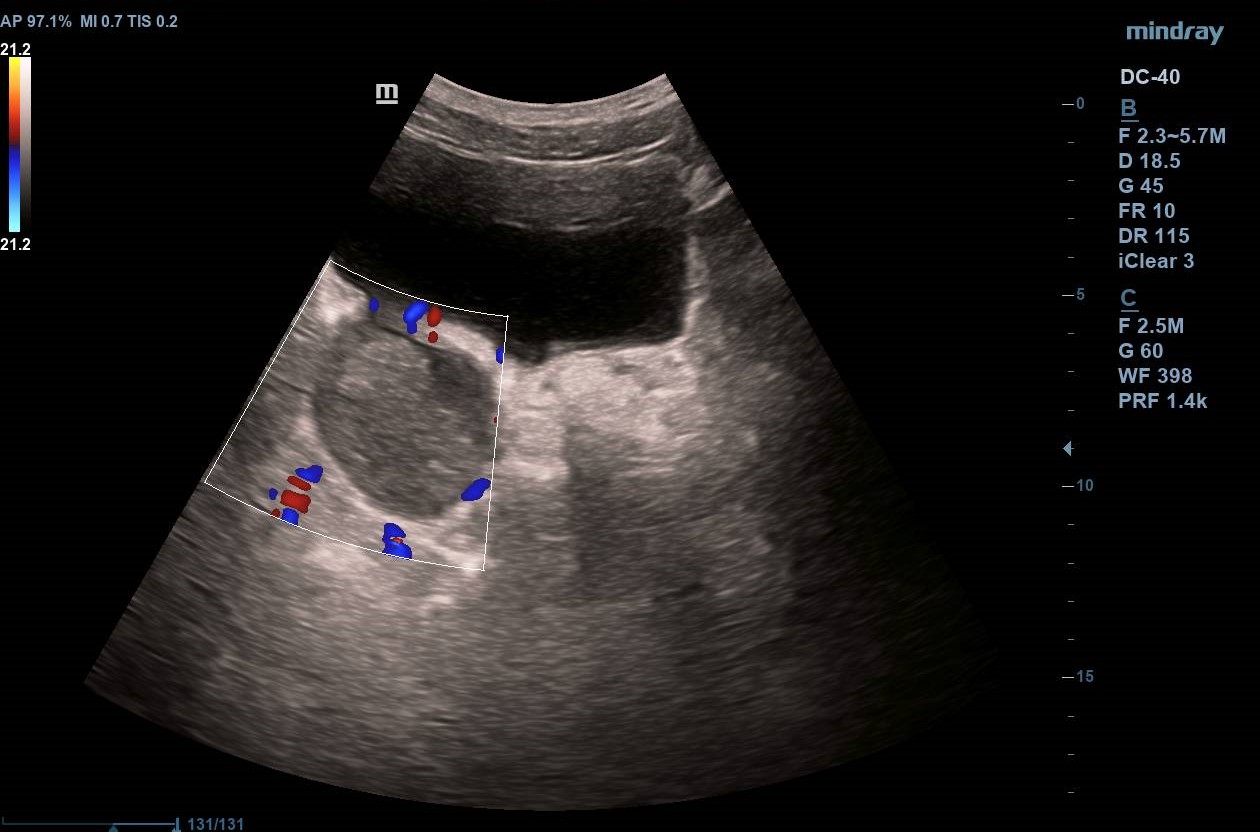

Divertículo vesical de 6 cm de diámetro en cuyo interior se observa masa homogénea de 4,43 x 3,15 cm que no capta Doppler y que parece depender de pared diverticular. Próstata homogénea de 37 cm3 (Imagen 1).

Masa vesical sospechosa de carcinoma de vejiga. Diagnóstico diferencial con coágulo vesical.